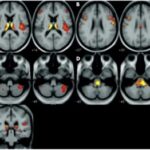

Se pueden mencionar al respecto los estudios que han encontrado en pacientes dependientes al alcohol una disminución del volumen de sustancia gris en el área de la corteza frontal, el hipocampo y el tálamo. El volumen de las sustancias blanca y gris también se puede ver disminuido en el área periventricular, la protuberancia y el cerebelo. Estos déficits de volumen también se han localizado en la corteza prefrontal dorsolateral derecha, ínsula anterior derecha, en el núcleo accumbens y en la amígdala izquierda(16) (ver Imagen 1).

Asimismo, como se indicó previamente, a través de la TC también se puede observar el deterioro de la microestructura cerebral por adicción al alcohol. El abuso de esta sustancia altera cinco fibras del cerebro, como el cuerpo calloso, el fondo de saco, la cápsula externa, el cíngulo circunvolución y el fascículo longitudinal superior, las que están involucradas en funciones como el procesamiento visoespacial y del lenguaje, la comunicación interhemisférica, la memoria, el procesamiento emocional, la toma de decisiones y la integración sensorial(16) (ver Imagen 2).